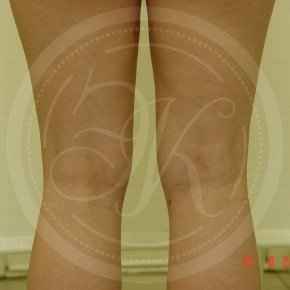

Фото до и после липосакции

В этой галерее мы публикуем снимки тех пациентов, которым была проведена липосакция. Фото до и после в полной мере позволяют оценить результат. Для каждого пациента мы подбираем тот вид вмешательства, который даст лучший результат при минимальном травматизме.